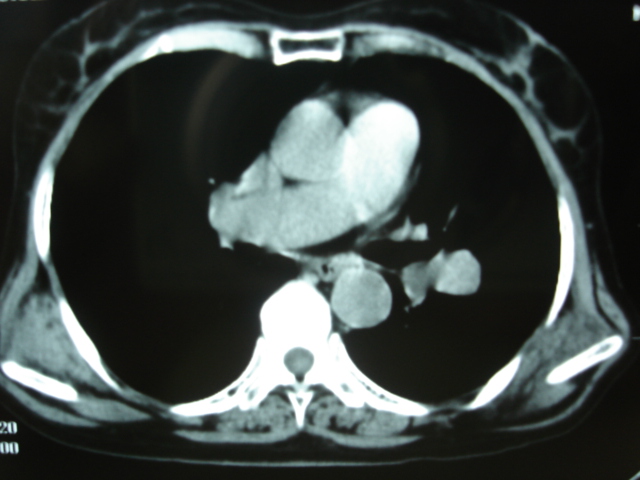

以下是引用卜一在2009-9-7 19:51:00的发言:[br][br] 1 左侧胸内甲状腺占位-多考虑甲状腺腺瘤! 2、左肺门占位-建议增强扫描以便明确性质。 3 慢支并感染! [br]

以下是引用shibing在2009-9-7 20:40:00的发言:[br]左侧胸内甲状腺占位-多考虑甲状腺腺瘤! 2、左肺门占位-建议增强扫描以便明确性质。 3 慢支并感染! [br]